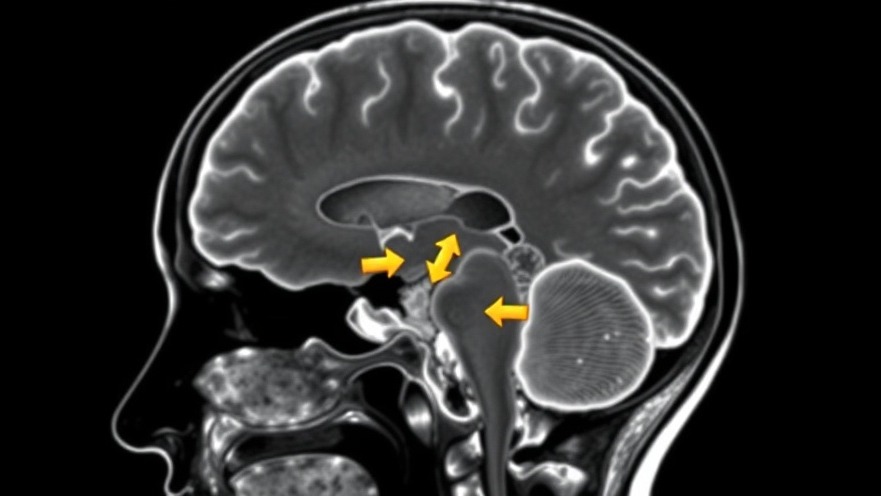

Facing a diagnosis of Chiari malformation (CM) or syringomyelia (SM) can be overwhelming, filled with a mix of physical and emotional challenges. Individuals often find themselves grappling not just with the medical implications of their condition, but also with profound feelings of isolation, uncertainty, and fear. Chiari, particularly Type I, involves structural abnormalities at the back of the skull affecting brain and spinal cord function, while syringomyelia refers to the formation of a cyst within the spinal cord caused by various factors, including Chiari malformation.